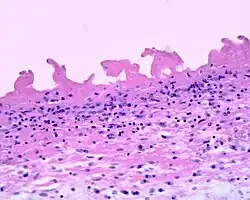

Fibrinous pericarditis is an exudative inflammation. The pericardium is infiltrated by the fibrinous exudate. This consists of fibrin strands and leukocytes. Fibrin describes an amorphous, eosinophilic (pink) network. Leukocytes (white blood cells; mainly neutrophils) are found within the fibrin deposits and intrapericardic. Vascular congestion is also present. Inflammatory cells do not penetrate the myocardium (as is seen with other presentations of pericarditis), and as a result, this particular variant does not present with diffuse ST elevation on ECG (a classic sign of pericarditis known as stage I ECG changes which are seen with other causes)[1] because the inflammatory cells do not penetrate the myocardium. To naked eye examination, this pathology is referred to as having a "Bread and Butter Appearance".